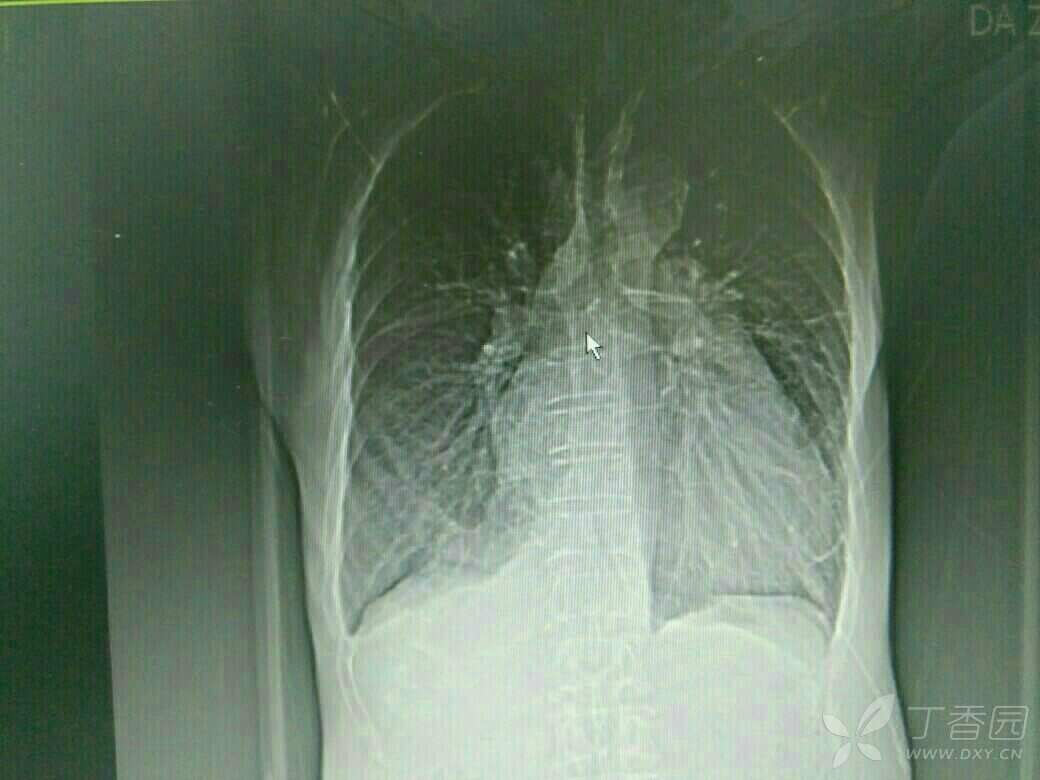

患者71岁老年男性,既往copd,多次住院治疗,平时状态好的时候气促也明显,这次是受凉在当地输液10多天,病情加重入院,来的时候诉乏力气促,上腹胀痛,不能进食,双下肢中度水肿,颈静脉怒张,肝功提示转氨酶400多,bnp6000多,心电图是快速房颤,心脏彩超示EF26%,CT示双侧胸腔积液,肝周积液,门静脉增宽,直径1.8cm,与强心利尿后,来的时候血气还可以,现在血气是呼酸合并代碱